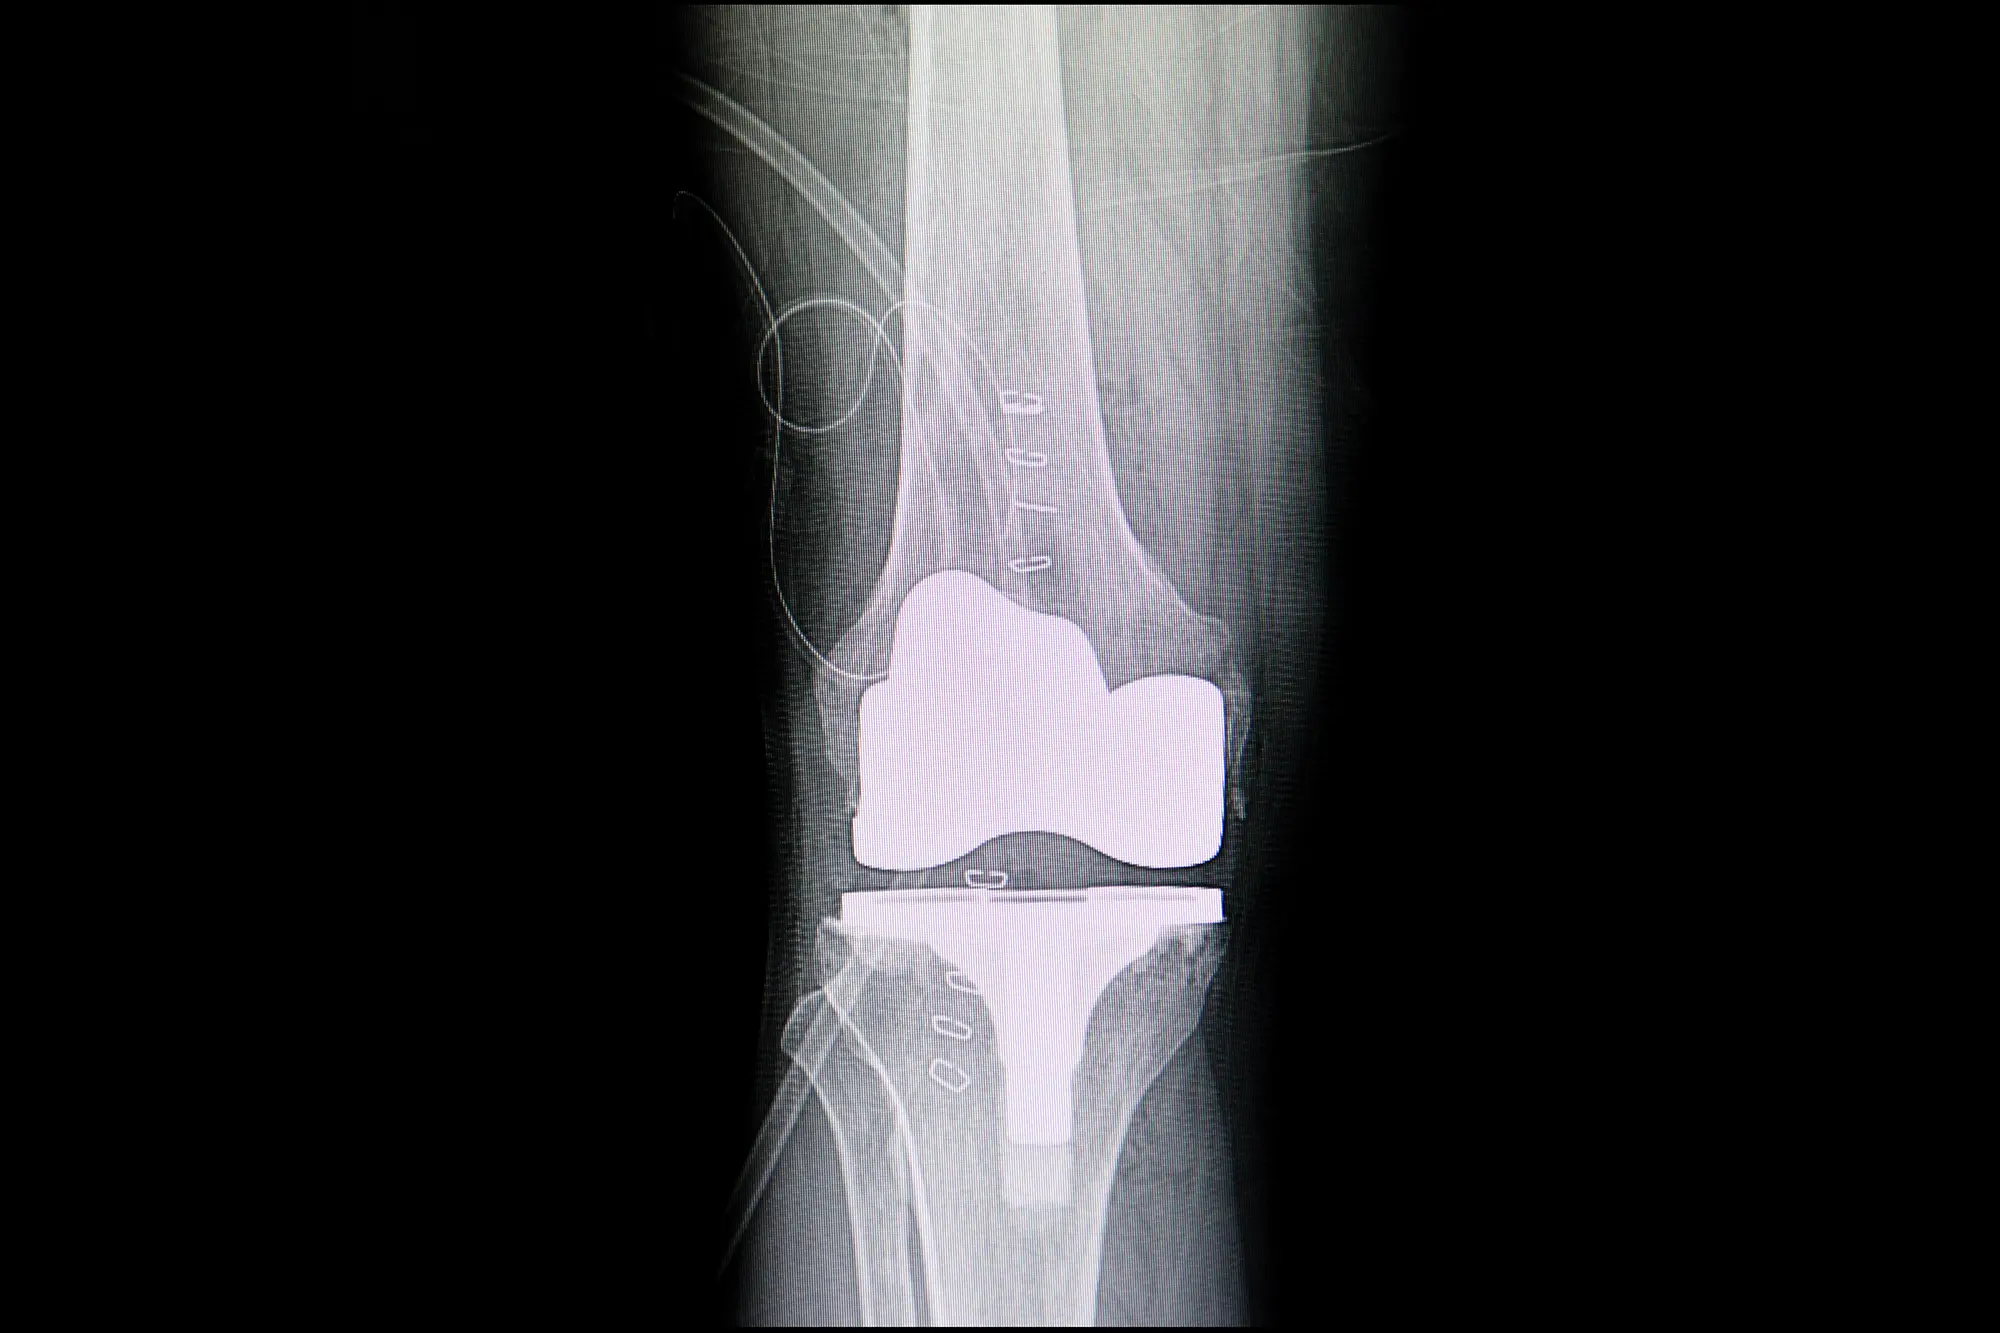

Las prótesis en 3D representan una revolución en la cirugía ortopédica. A diferencia de las prótesis tradicionales, estas se diseñan de forma personalizada a partir de la anatomía del paciente mediante tecnología de imagen y modelado digital.

El uso de prótesis en 3D mejora significativamente los resultados de las cirugías articulares. Los pacientes experimentan una mejor movilidad, menos molestias postoperatorias y una recuperación más eficiente.

Además, al tratarse de una solución personalizada, se minimizan los riesgos y se optimiza el resultado funcional a largo plazo.